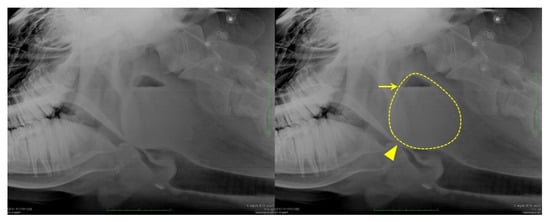

Figure 1. Lateral radiography of the pharyngeal area of the cow showing a retropharyngeal abscess obstructing the laryngeal airway (arrowhead). The dashed line indicates the mass outline, and the arrow points to the horizontal demarcating line, which indicates the presence of fluids.